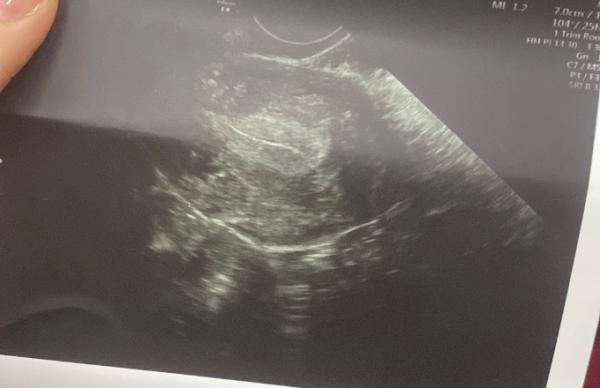

Hallo liebe Leute, ich befinde mich aktuell in der 4+5 ssw und mein hcg wert ist heute bei 716 vor 3 Tagen war es bei 360 also schlägt es sehr langsam an und man konnte heute beim Ultraschall nur das hier (siehe Bild) sehen. Meine Periode ist aber komischerweise erst in 8 Tagen fällig das heißt die soll erst in 8 Tagen kommen. Ich verstehe die Welt nicht mehr.. kann mir bitte einer helfen

Bild zu 4+5 ssw nichts im Ultraschall zu sehen - Schwanger - wer noch? Rund um die Schwangerschaft

Hallo, der Arzt hat es so ausgerechnet das ich wohl seit 4+ 5 Wochen schwanger bin, was ich auch nicht verstehen kann ich hatte am 10.12 meinen letzten Periode Tag und genau da auch GV und meine App zeigt mir an das mein ES am 22 statt gefunden hätte ich hatte aber genau da ein Tag davor ganz bisschen Schmier blut und zwei Tage danach hab ich aus Spaß einen sst gemacht der war positiv dann waren wir beim Frauenarzt und man konnte beim Ultraschall einfach nichts sehen daher wurde Blut abgenommen zuerst war mein hcg bei 277 zwei Tage danach bei 360 und 3 Tage danach 716 und heute konnte man nur das oben auf dem Ultraschall Bild sehen.. und am Dienstag sollen wir wieder dahin obwohl meine Periode erst in 8 Tagen kommen sollte ich verstehe wirklich selber nichts